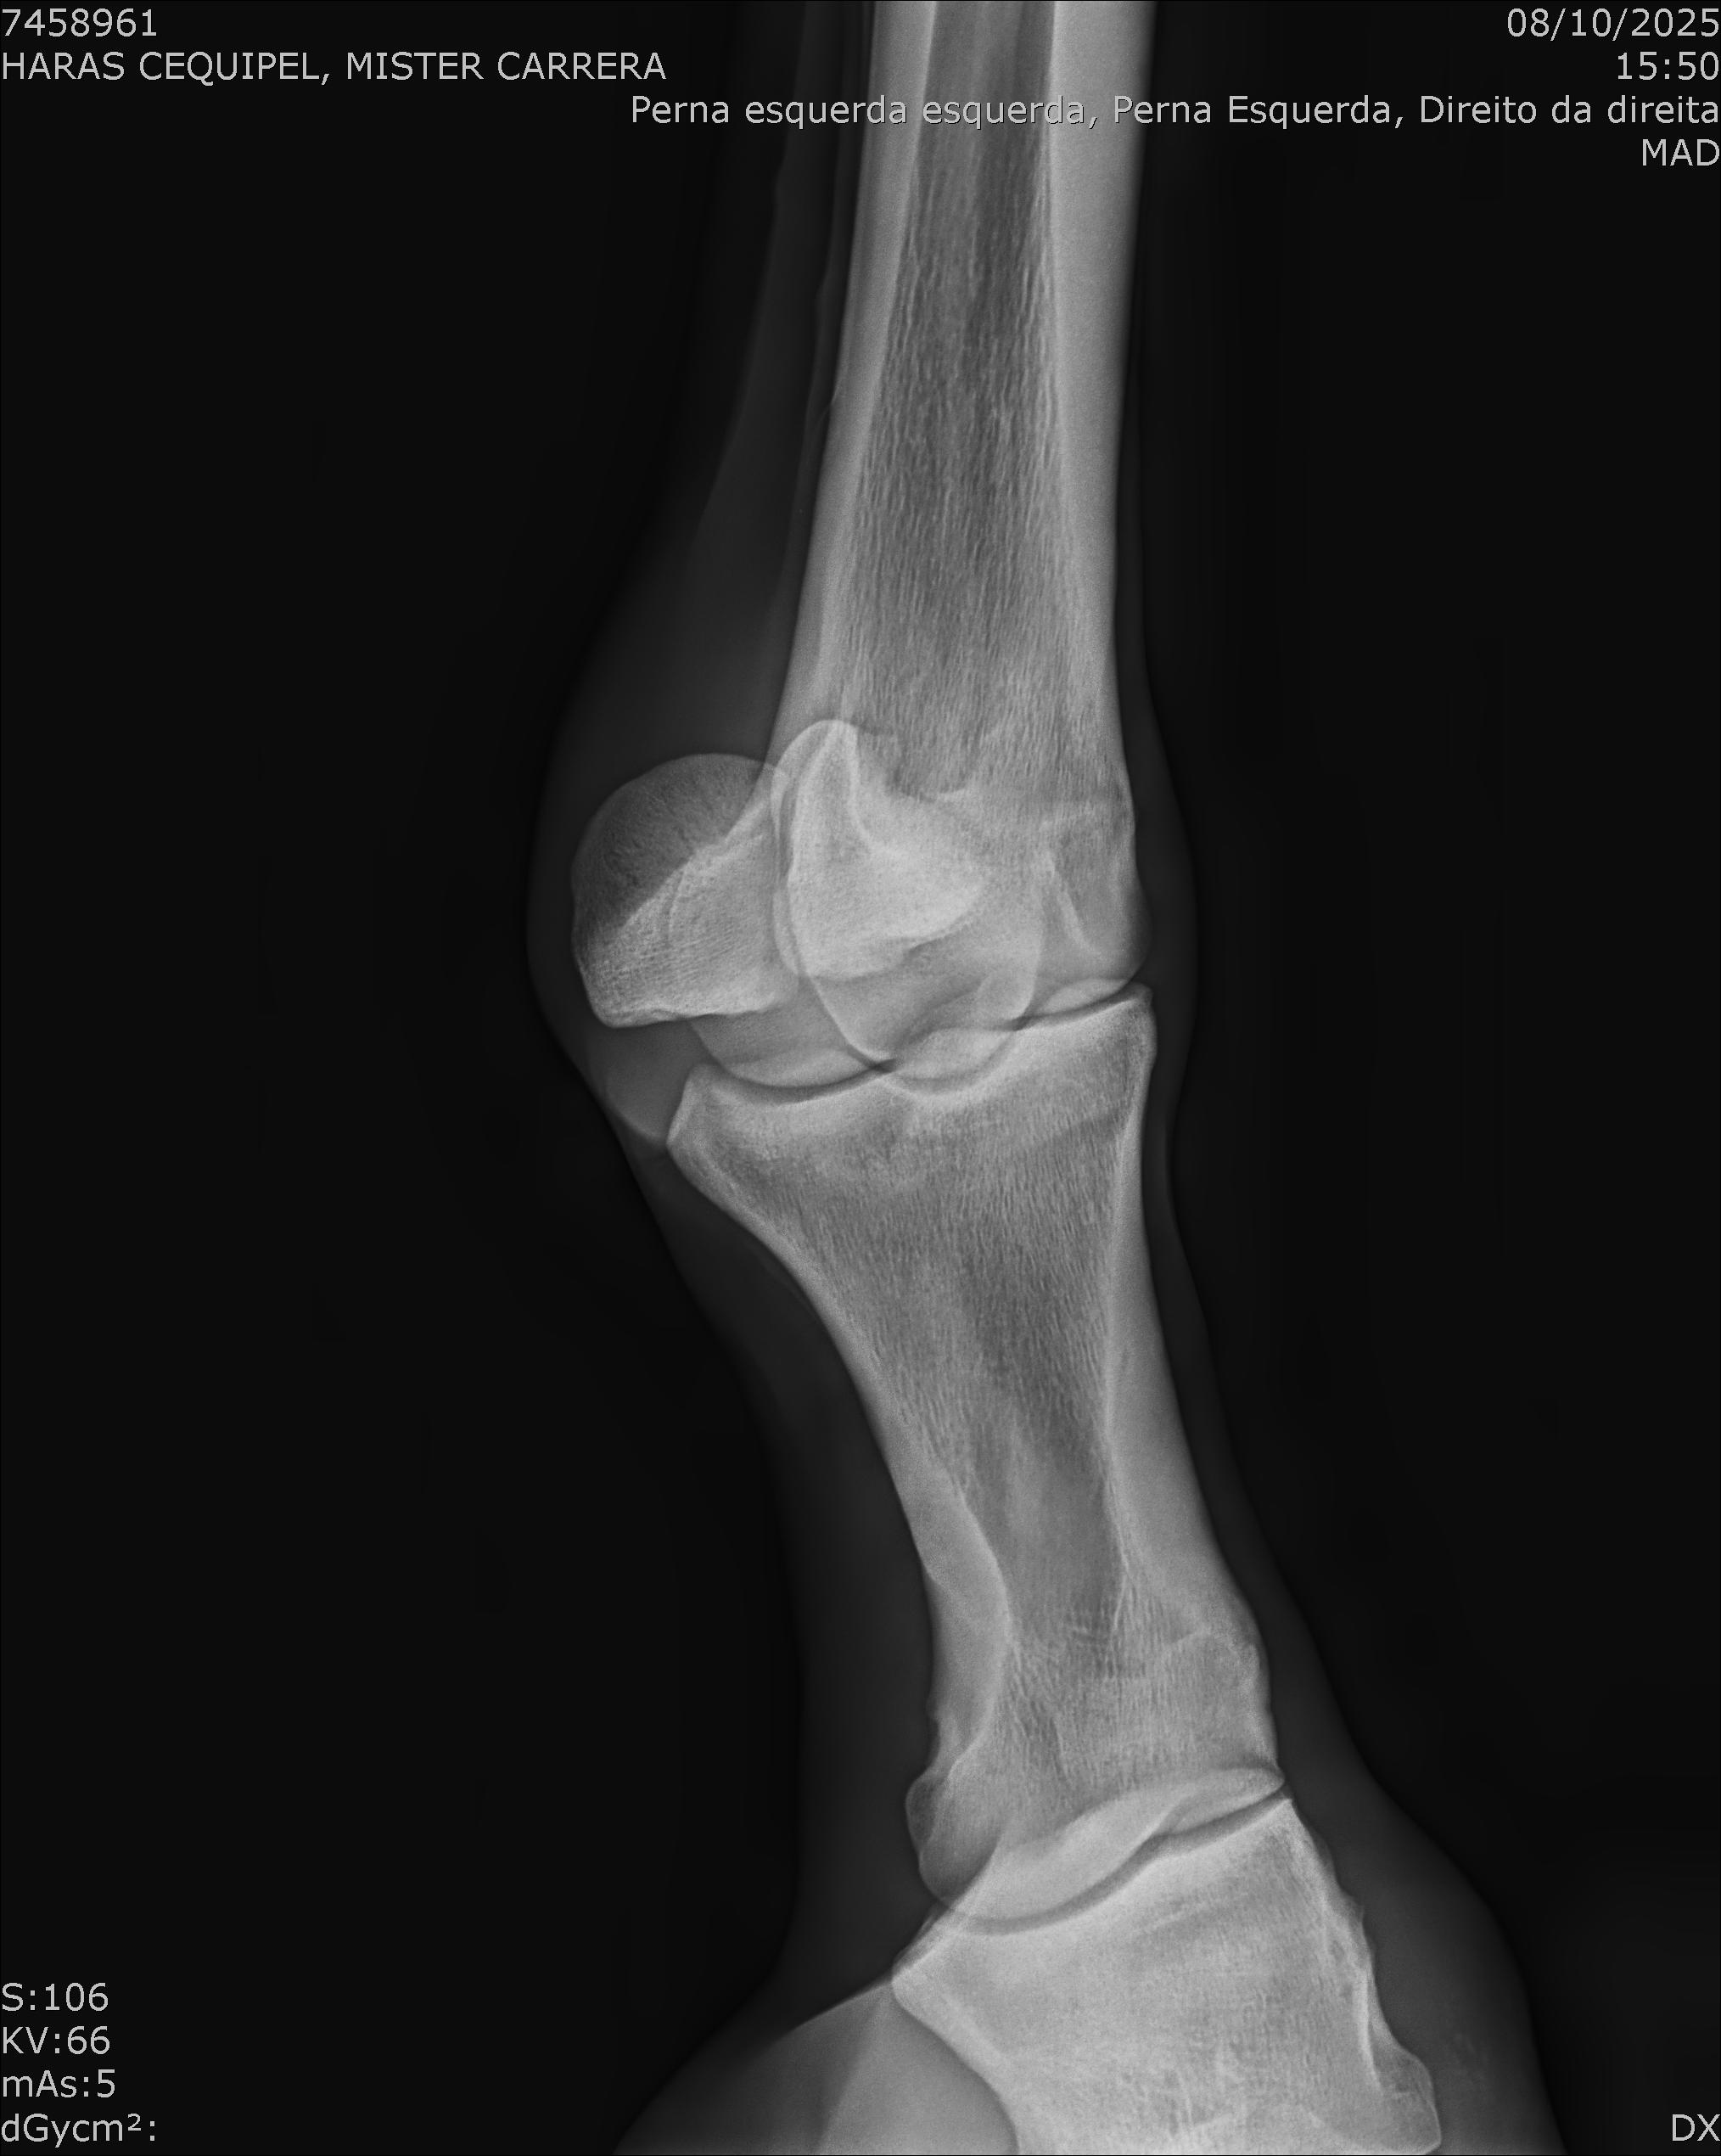

:: RAIOS-X DO LOTE